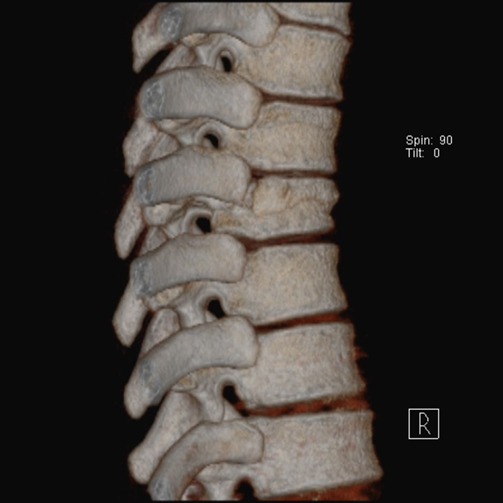

(3)burst骨折

椎体轴向压力造成的骨折,通常发生骨折碎片向四周移位,有时候可以突入椎管。可以发生在颈椎、胸椎或腰椎。